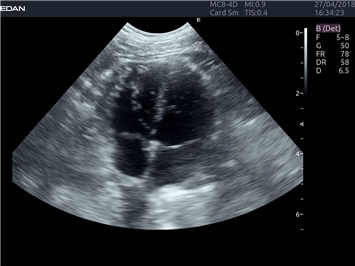

EDAN Acclarix LX4 VET

EDAN Acclarix LX4 VET представляет собой профессиональную ультразвуковую систему, специально разработанную для ветеринарных исследований. Сочетание стабильности, высокой производительности и эффективности делает эту систему идеальным выбором для современной ветеринарной практики.

• Адаптивная визуализация тканей:

• Оптимизация изображения для различных видов животных

• Улучшенная детализация структур

• Мультилучевое сложно-составное сканирование (SCI):

• Повышенная четкость изображения

• Улучшенная визуализация сложных анатомических структур

• Технология подавления зернистости:

• Снижение шумов изображения

• Повышение диагностической ценности